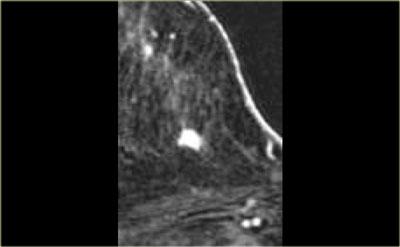

Hình ảnh bên trái cho thấy một khối ngấm thuốc ở vú trái.

Đây được xác định là ung thư xâm lấn.

Phía ngoài khối là một vùng ngấm thuốc không tạo khối theo ống tuyến, được xác định là DCIS.